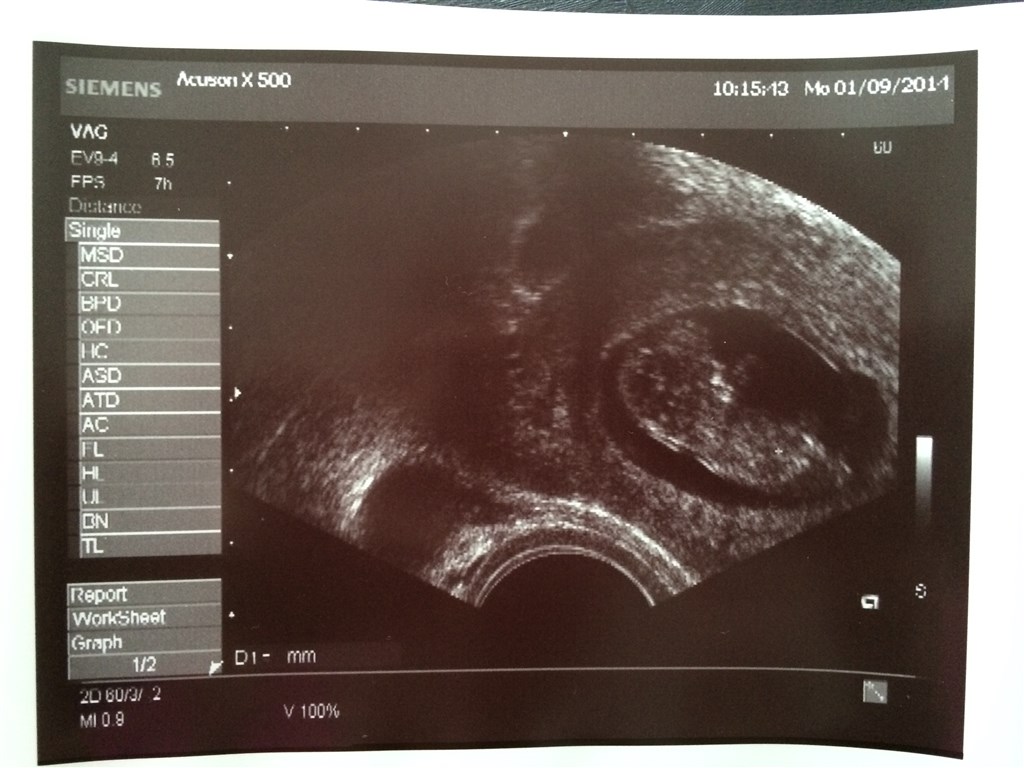

Var til scanning igår, der var det smukkeste hjerte blink.

Blev dog rykket tilbage i termin, er 6+2 idag

Vedhæftede fotos (klik for at se i fuld størrelse)